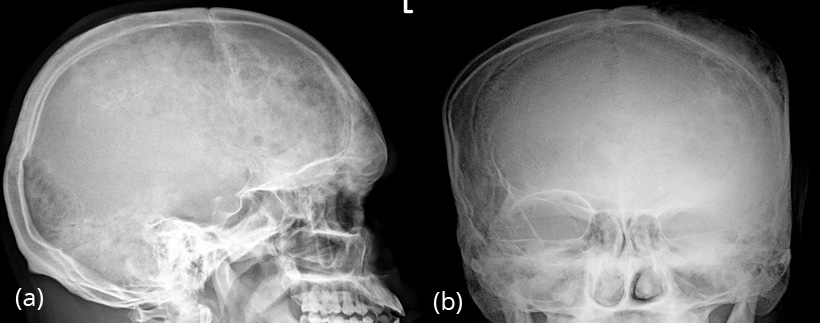

Occasionally, moth eaten appearance may be seen, simulating metastasis or myeloma (Figure 4ab). The age of the patient often differentiates from other lesions.

Figure 4a,b: FD skull in a 24yr old. Note the moth eaten appearance of the frontoparietal bones.